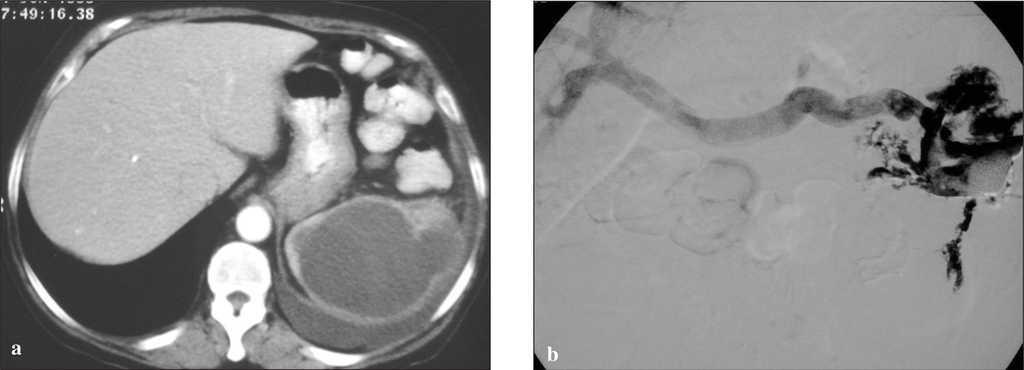

No se han descrito complicaciones con el uso de fibrinolÃticos como tratamiento coadyuvante de colecciones abscesificadas abdominales; sin embargo, su utilización incorrecta podrÃa producir hemorragias intraabsceso, sangrado de aneurismas, seudoaneurismas o malformaciones (fig. 4 a y b).

Fig. 4. Complicación postratamiento mediante drenaje con catéter y urocinasa. a) TomografÃa computarizada de un paciente con fiebre y absceso en la celda esplénica postesplenectomÃa en una resección de carcinoma de ángulo esplénico. b) Cavitograma posdrenaje con catéter y urocinasa que muestra el relleno de la vena porta. La paciente no requirió tratamiento complementario y se mantuvo el drenaje cerrado durante 2 dÃas. Se abrió y se mantuvo abierto sin fibrinolÃtico durante una semana y se retiró sin consecuencias.